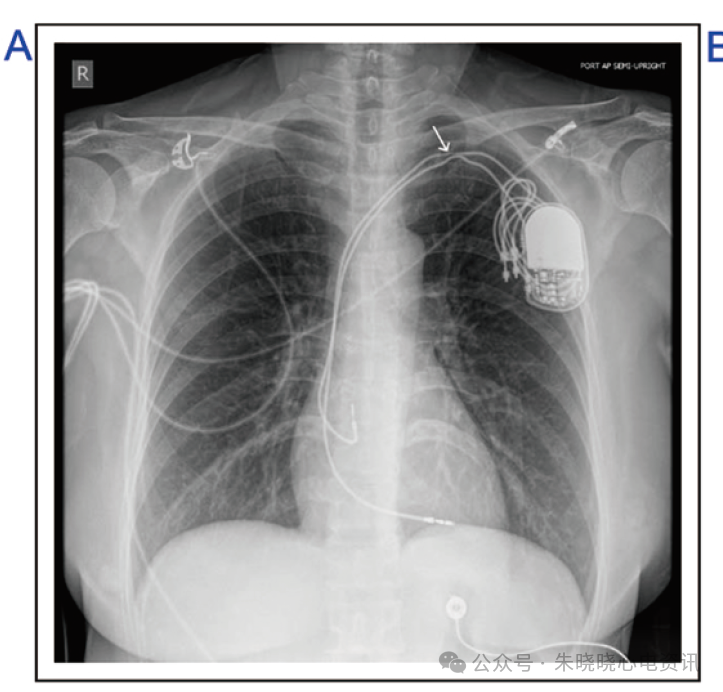

锁骨下挤压综合征是引起起搏功能障碍的一个明确原因,这是起搏电极导线经锁骨下静脉入路进人体内时,因各种原因使其入路位于患者第一肋骨和锁骨间的最窄部位,进而使电极导管在此处受到压迫,引起电极导线的绝缘层破坏或电极导线的断裂,进而引起相应的起搏或感知功能的障碍(图1A、B)。

除在患者胸片可看到电极导线明确受压或断裂外,患者起搏心电图可能存在着明确的起搏或感知功能障碍(图1B)。